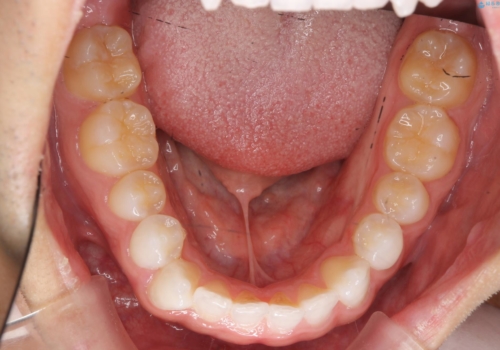

- 舌小帯の切除を希望して来院。

口を大きく開けた時に、上顎に舌がつかない状態でした。